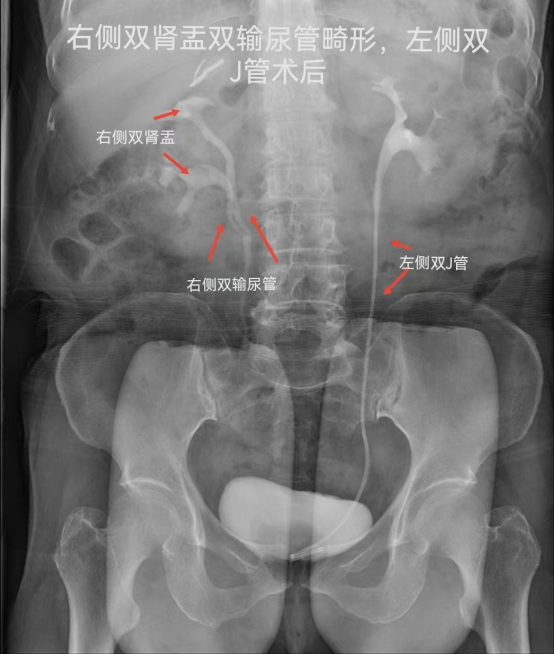

常规拍腹部仰卧位平片(KUB),准备好腹部压迫带,静脉注射造影剂,同时腹部加压,注射完后分别于7、15、30分钟摄片及解除压迫后摄片。

IMG_259IMG_260IMG_261IMG_262

静脉肾盂造影用于检查泌尿道器质性病变,可观察到尿路梗阻部位及原因。显示尿路结石造成的造影充盈缺损,对泌尿系病变有重要的诊断意义,静脉肾盂造影是放射科的常规检查项目,为进一步治疗提供可靠的指导意见及治疗方案。(供稿:放射科)